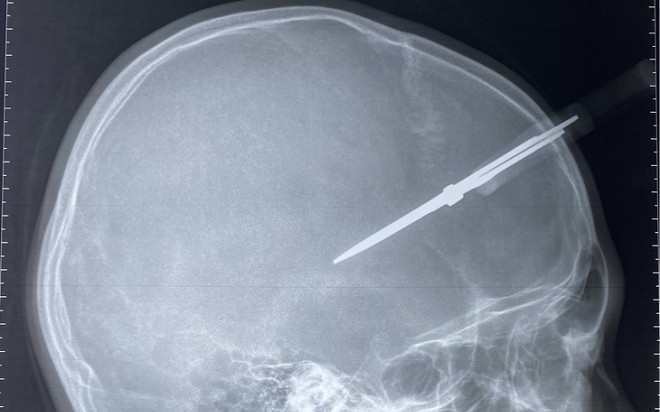

Ngày 19/1, thông tin với TTO, Bệnh viện Đa khoa Đức Giang (Hà Nội) cho hay vừa tiếp nhận cấp cứu trường hợp bé P.T.H. (12 tuổi, Hà Nội) bị kéo đâm thủng hộp sọ.

Được biết thời điểm nhập viện, bệnh nhân trong tỉnh trạng tỉnh táo, cây kéo cắm chặt vào vùng thái dương phải. Qua chụp phim cho thấy cây kéo đâm qua xương sọ vào trong hộp sọ.

Bác sĩ  Trần Minh Tân - Khoa Cấp cứu, Bệnh viện Đa khoa Đức Giang nhận định, các trường hợp bị dị vật đâm thủng hộp sọ có nguy cơ bị chảy máu não. Trường hợp này, vị trí của cây kéo nằm ở vùng thái dương, nơi có động mạch màng não giữa đi qua, rất có thể gây đứt động mạch, dẫn đến máu tụ ngoài màng cứng. Nếu không xử lý sớm, bệnh nhân có nguy cơ áp xe não, viêm màng não về sau.

Sau khi tiến hành các bước cấp cứu, hổi chẩn, làm xét nghiệm, ekip tiến hành chuyển phẫu thuật cho bé trai. Trong ca mổ, bác sĩ mở rộng vết thương, mở xương sọ, lấy bỏ cây kéo khỏi hộp sọ của bệnh nhi, làm sạch dị vật tóc, xương vụn, lấy máu tụ, cầm máu.